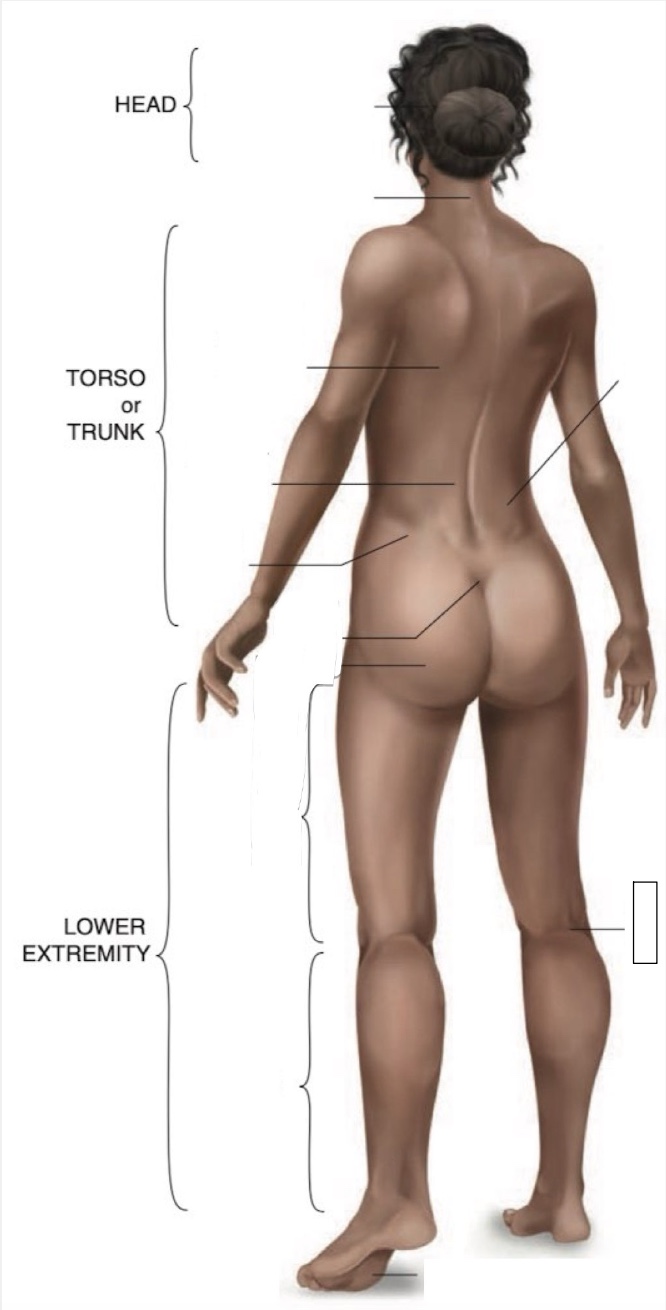

Occipital region

Cervical region

Inferior angle of scapula

Lumbar region

Iliac crest

Sacral region

Buttock

Thigh

Leg

Flank

Popliteal region